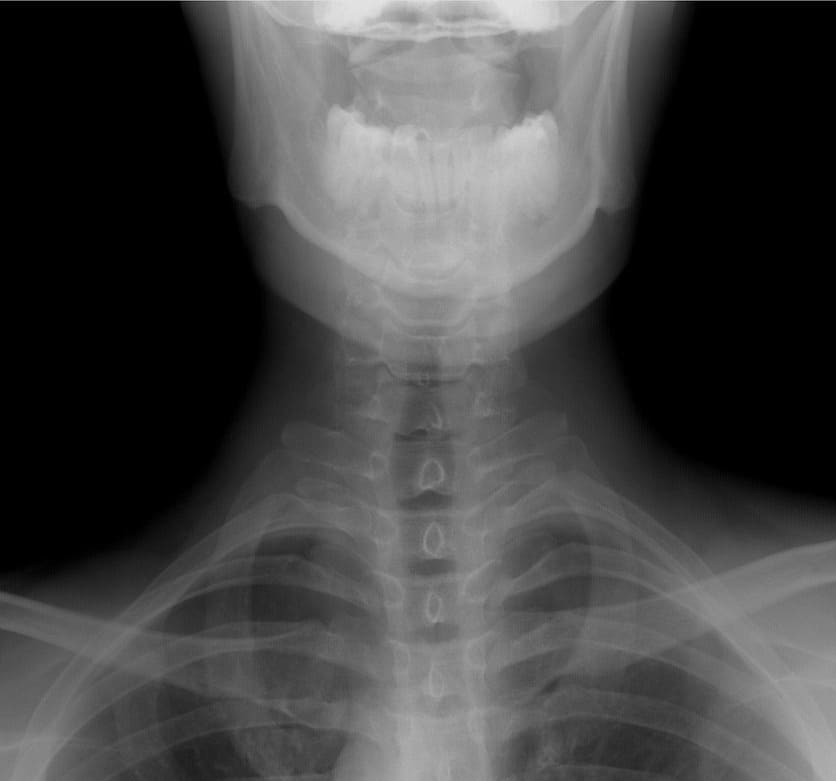

목디스크 정확한 진단 방법과 검사법

- X-ray 검사: 척추 배열과 퇴행성 변화를 확인